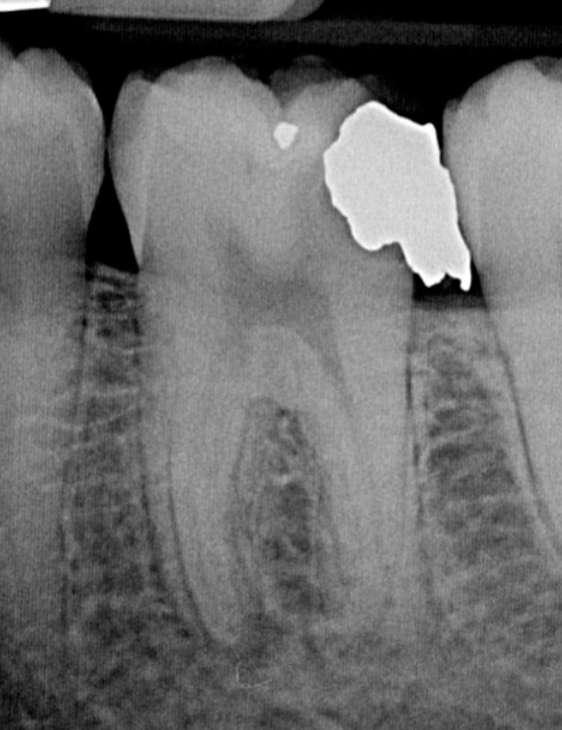

Röntgenologischer Befund:

Das präoperativ angefertigte Röntgenbild (Abbildung 10) zeigt den bereits vom Vorbehandler trepanierten Zahn 27. Die Wurzelfüllung erscheint inhomogen. Das Wurzelfüllmaterial im mesiobukkalen Kanal ist über den röntgenologischen Apex hinaus extendiert und es zeigt sich eine periapikale Osteolyse der mesiobukkalen Wurzel.

Abbildung 10: Präoperative diagnostische Aufnahme